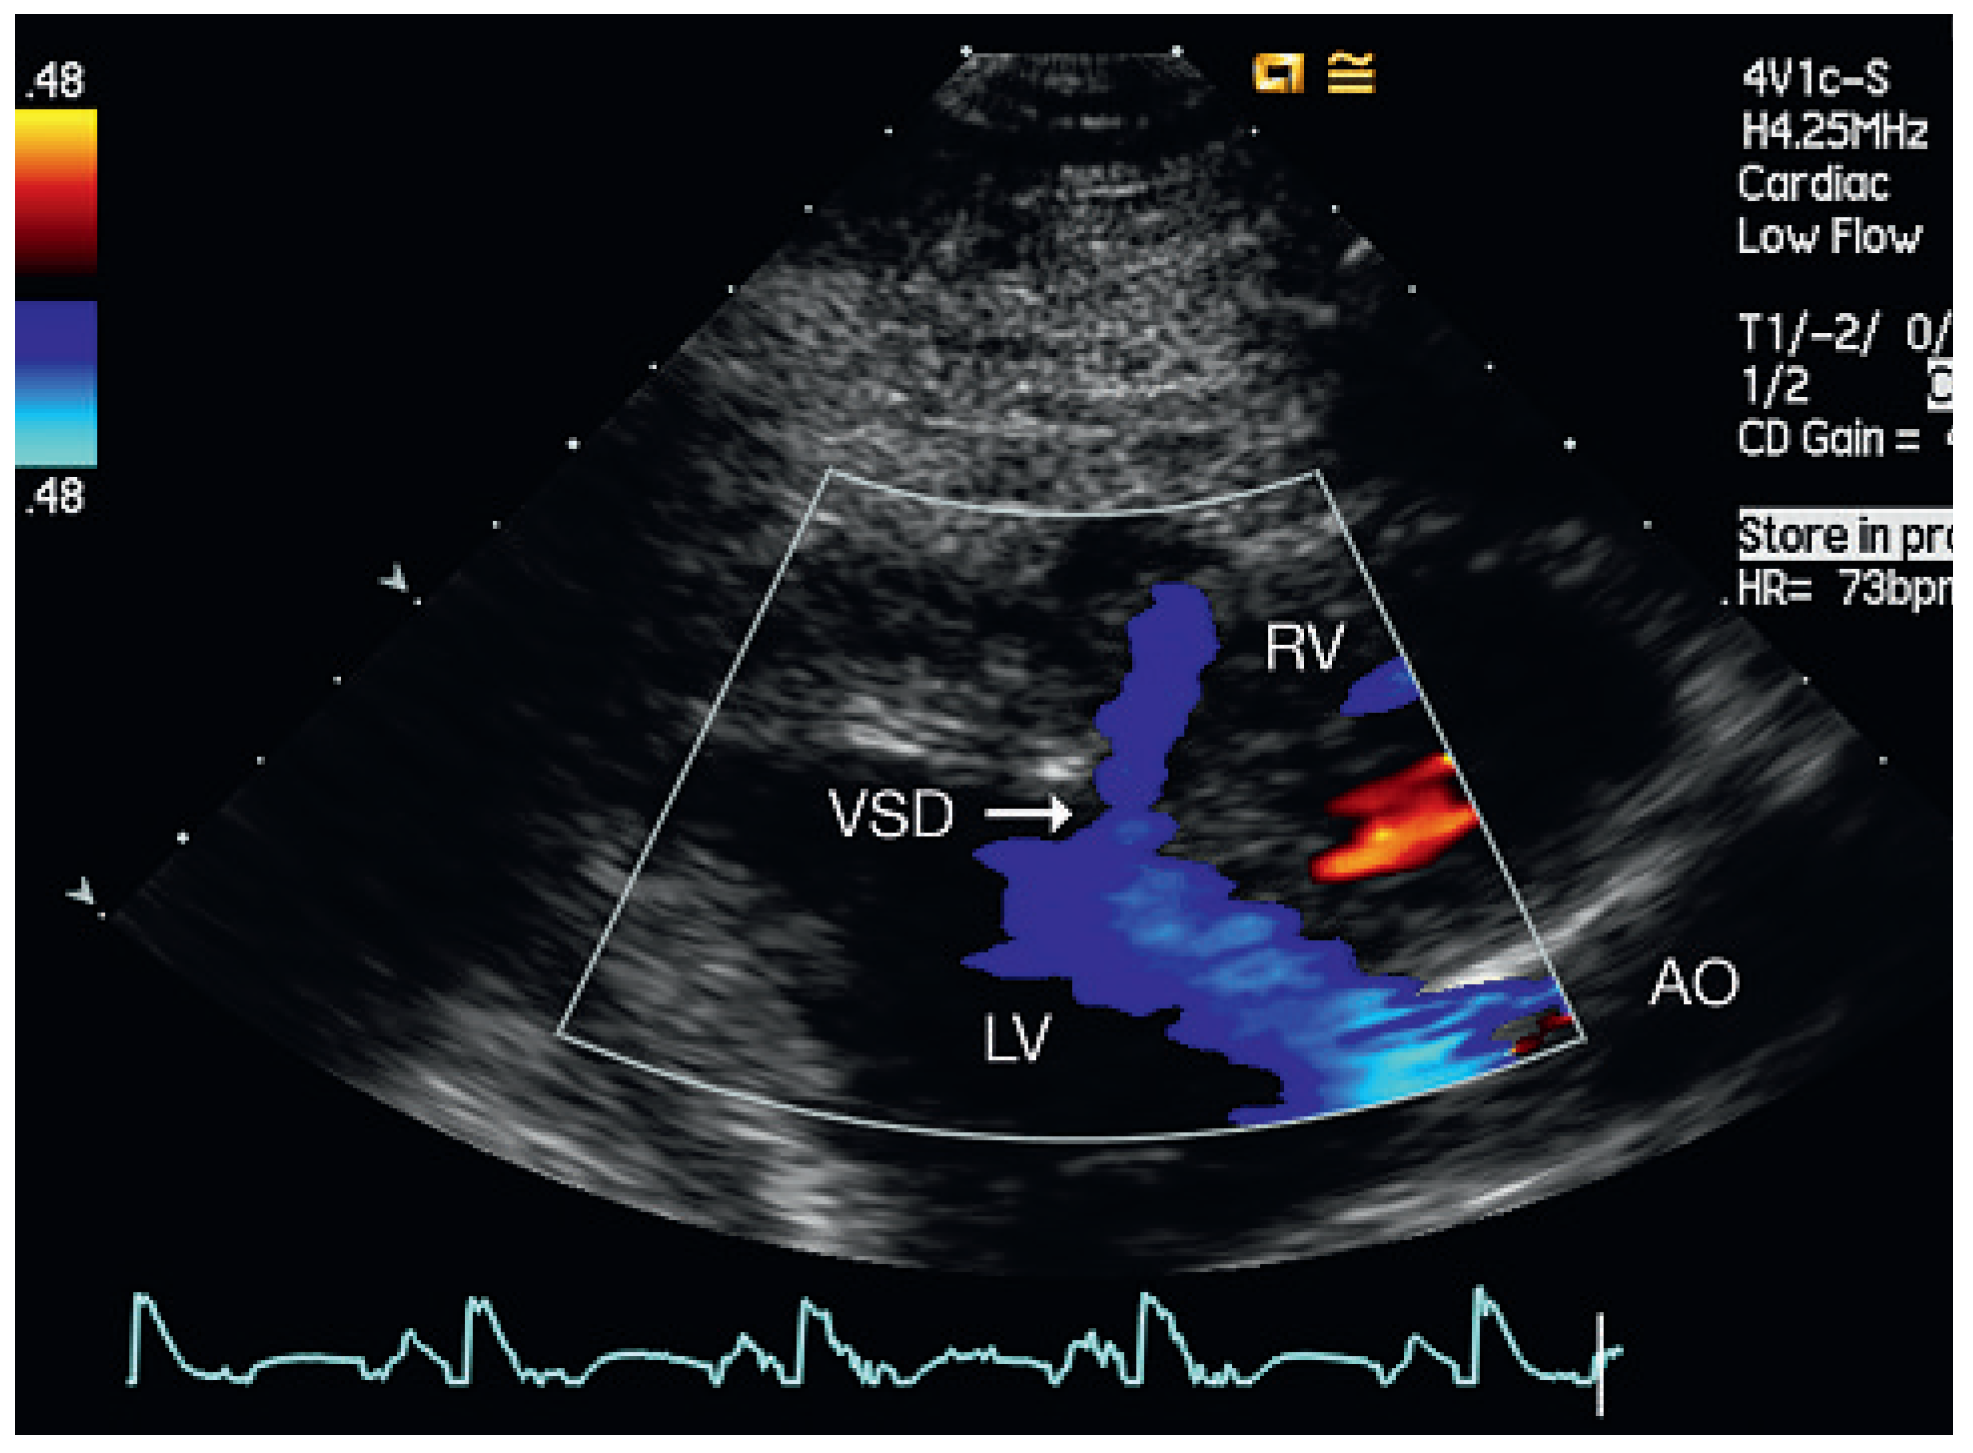

Figure 6.

Patient 5, at admission. Parasternal long-axis view (LV outflow): muscular VSD mid-anteroseptal. AO = aorta; LV = left ventricle; RV = right ventricle; VSD = ventricular septal defect.

From September 2007 to December 2008, five patients aged 54–69 years were admitted to our institution for cardiac rehabilitation after surgical cardiac valve replacement (Table 1). Successful replacement of the aortic valve was performed in four of the patients and mitral valve replacement in the other. All patients received mechanical prosthetic valves (ATS medical) and had a history of dyspnoea, fatigue and exercise limitation. Physical examination on admission did not reveal signs of congestion in any of the patients. The admission electrocardiogram showed sinus rhythm or atrial fibrillation (patient 4) and signs of left ventricular hypertrophy in 3 of 5 patients. Doppler echocardiography revealed a restrictive muscular ventricular septal defect (Figure 1, Figure 3, Figure 4, Figure 5 and Figure 6) with Qp/Qs < 1.4 in all of the patients. The function of the prosthetic valves was normal and in one patient (patient 5) systolic pump function was moderately reduced.

Echocardiographic follow-up revealed spontaneous closure of the septal perforation in four of the five patients (Figure 2). In one patient the septal defect persisted for one and a half years after surgery, but he remained asymptomatic without deterioration of left ventricular function or increased pulmonary artery systolic pressure.